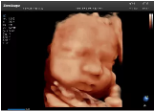

4容積探頭

積探頭是在二維圖像的基礎上,將連續(xù)采集的空間分布位置,經(jīng)過計算機重建算法,從而獲得完整的空間形態(tài)。

適用于:胎兒面部、脊柱和肢體等。

優(yōu)勢特點:快速獲取、掃查連續(xù)均勻、解剖結(jié)構(gòu)顯示為容積數(shù)據(jù)、準確進行容積測量。